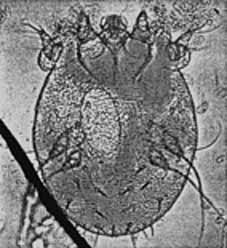

La SCABBIA [in antico si usava genericamente il termine ROGNA che attualmente è esteso solo al mondo animale ma ha grandi prossimità patologiche] è una malattia infettiva altamente contagiosa, l’agente causale è l’acaro (SARCOPTES SCABIEI).

Gli acari della scabbia sono diffusi in tutto il mondo ed appartengono all’ordine degli Artropodi. Come tutti gli acari, anche quello della scabbia trascorre tutte le fasi del ciclo vitale su animali a sangue caldo (uomo-animali), possiede quattro paia di zampe, e riesce ad invadere gli strati più superficiali dell’epidermide, formando gallerie che si estendono a volte fino allo strato granuloso.

Le femmine a temperature superiori ai 20-25° C sono particolarmente mobili e sono quindi capaci di penetrare nell’epidermide, in appena 20 minuti, per una profondità di 2,5-3 cm. Ciascuna femmina depone dalle due alle quattro uova al giorno. Dopo circa cinque giorni fuoriescono le larve (larve d’acaro) queste ultime subiscono tre mutazioni prima di trasformarsi in elementi adulti , capaci di accoppiarsi ed iniziare cosi’ di nuovo la deposizione delle uova. Il ciclo vitale dura 14-17 giorni.